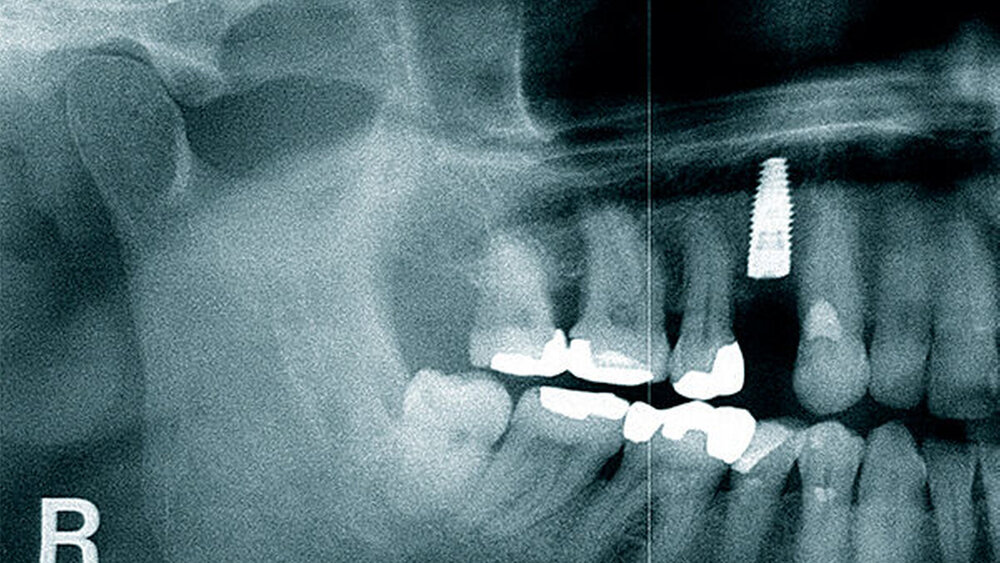

Der folgende klinische Fall dokumentiert die Behandlung eines 61 Jahre alten Patienten, der sich initial mit erheblichen Beschwerden an Zahn 14 vorgestellt hatte. Die radiologische Untersuchung (Abb. 1) ergab eine periapikale Aufhellung sowie eine insuffiziente Wurzelkanalbehandlung. Im Folgenden wurde die Krone entfernt und eine Revision der Wurzelkanalbehandlung durchgeführt. Im Rahmen der Revisionsbehandlung stellte sich eine Längsfraktur im Bereich der vestibulären Wurzel dar. Aufgrund der daraus resultierenden schlechten Prognose einer weitführenden konservierenden Therapie wurde der Zahn atraumatisch entfernt und die Alveole sorgfältig von Granula‧tionsgewebe und einem sich apikal befindenden Zystenbalg befreit (Abb. 2). Das gewonnene Gewebe wurde der histopathologischen Untersuchung zugeführt; dabei ergab sich das Bild einer radikulären Zyste. Aufgrund der latent vorhandenen Inflammation im Bereich der Alveole wurde auf eine sofortige Augmentation mit Knochenersatzmaterial im Sinne einer Ridge Preservation verzichtet. Die Alveole wurde konventionell mit einem Kollagenkegel und einer adaptierenden Naht versorgt. Nach Besprechung mit dem Patienten wurde eine implantatprothetische Versorgung geplant. In der ersten chirurgischen Phase (sechs Wochen nach der Extraktion) erfolgte ein horizontaler Alveolarkammaufbau mittels GBR-Technik unter Lokalanästhesie, um das abgebaute Knochengewebe wiederherzustellen und damit ein entsprechendes Implantatbett zu gestalten. Präoperativ zeigten sich vestibulär in regio 14 sowohl der Knochen als auch das Weichgewebe defizitär (Abb. 3). Im Rahmen der geplanten Augmentation erfolgte die Bildung eines lokalen Mukoperiostlappens in regio 14. Aufgrund der aus den vorhergegangenen operativen Eingriffen resultierenden Narbenzüge im OP-Gebiet wurde auf eine gängige Lappenextension über das Augmentationsgebiet hinaus verzichtet. Nach Lappenbildung konnte der wandige Defekt exploriert und intensiv mit physiologischer Kochsalzlösung gespült werden (Abb. 4). Im Anschluss erfolgten die Vorlage einer neuen nicht resorbierbaren Membran (permamem, botiss biomaterials, Zossen, Deutschland) sowie der Zuschnitt der Membran entsprechend der Größe des abzudeckenden Defekts (Abb. 5). Es folgte die Augmentation des wandigen Knochendefekts mit allogenem Knochenersatzmate‧rial (maxgraft spongiöse Granula, botiss biomaterials), das zuvor mit venösem Eigenblut des Patienten durchmischt worden war (Abb. 6 und 7). Danach wurde das Augmentat mit der vorgelegten nicht resorbierbaren Membran abgedeckt (Abb. 8). Der Wundverschluss erfolgte mittels horizontaler Matratzennaht und Einzelknopfnähten (Resolon 4.0/5.0, Resorba, Nürnberg, Deutschland) (Abb. 9). Die postoperativ angefertigte Halbseiten-Panoramaschichtaufnahme zeigte eine vollständige Augmentation der Defektregion (Abb. 10).

Die klinische und radiologische Verlaufskontrolle sechs Monate nach der GBR zeigte eine suffiziente Weichgewebssituation sowie ein solides knöchernes Implan‧tatlager in regio 14 bei mehr als 8 mm periimplantär fixierter Gingiva (Abb. 12 und 13). Für die eigentliche Implantation wurde ein Mukoperiostlappen geringer Ausdehnung gebildet und der augmentierte Bereich anteilig wiedereröffnet. Eine gute knöcherne Regeneration der ehemaligen Zahnalveole wurde dabei sichtbar (Abb. 14). Die allogenen Knochenpartikel waren fest in das neugebildete Knochengewebe integriert, Anzeichen von Bindegewebseinkapselung waren nicht sichtbar. Ein Titanimplantat (Straumann Bone Level Tapered, Institute Straumann AG, Basel, Schweiz) wurde mittels Bohrschablone gemäß der 3D-Planung an Position 14 – 2 mm subkrestal – inseriert und einer geschlossenen Einheilung überlassen (Wundverschluss Resolon 6.0, Resorba, Nürnberg, Deutschland). Die Implantatposition wurde postoperativ mittels Panoramaschichtaufnahme überprüft (Abb. 15). Vier Monate nach der Insertion wurde das Implantat freigelegt und ein individualisierter PEEK-Gingivaformer eingesetzt (Abb. 16). Bereits drei Wochen später folgte die prothetische Versorgung mithilfe einer verschraubten Metallkeramikeinzelkrone auf einem Titanimplantataufbau (Abb. 17 und 18). Eine Individualisierung der Farbgebung im Bereich des Kronenhalses wurde seitens des Patienten bei der Anprobe abgelehnt. Die Position der Krone wurde radiologisch dokumentiert und dient, zusammen mit den entsprechenden Sondierungstiefen, zur Verlaufskontrolle der Umbauvorgänge im Bereich des periimplantären Gewebes (Abb. 19).